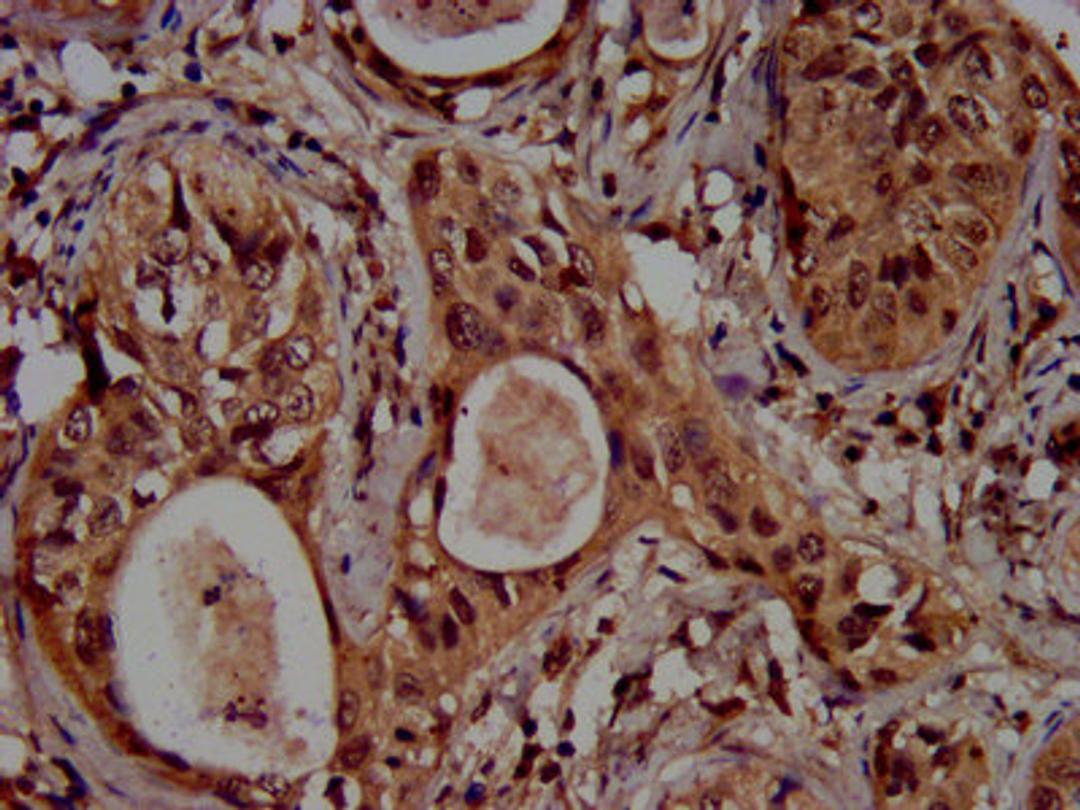

IHC image of CSB-PA010418OA04ncrHU diluted at 1:100 and staining in paraffin-embedded human cervical cancer performed on a Leica BondTM system. After dewaxing and hydration, antigen retrieval was mediated by high pressure in a citrate buffer (pH 6.0). Section was blocked with 10% normal goat serum 30min at RT. Then primary antibody (1% BSA) was incubated at 4°C overnight. The primary is detected by a biotinylated secondary antibody and visualized using an HRP conjugated SP system.